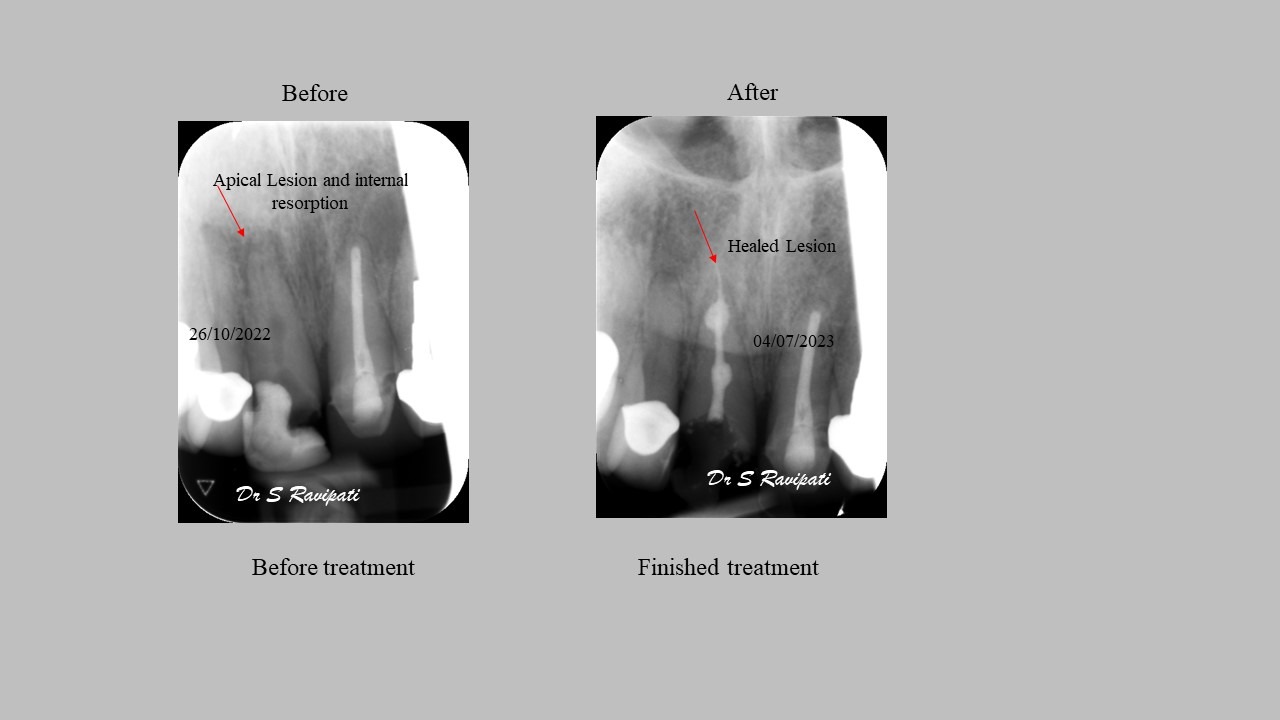

The main goal of endodontic therapy is to remove necrotic pulp tissues, to eliminate or significantly reduce microorganisms and their toxic products from the canals and also to prevent inflammatory lesion in the periapical area. Endodontic therapy protects the tooth from further invasion from microorganisms. If the tooth is left without treating, the infection may spread and cause pain and swelling.

Studies have shown thorough cleaning with instruments, disinfection and sealing the canals contribute to the successful healing of the infection and this success is reported as 95%.